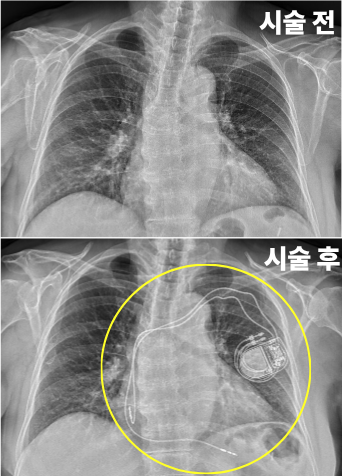

✅ 심박동기 삽입술

: 서맥 환자에게 인공 심박동기를 삽입해 정상 심박수를 유지하는 치료법입니다.